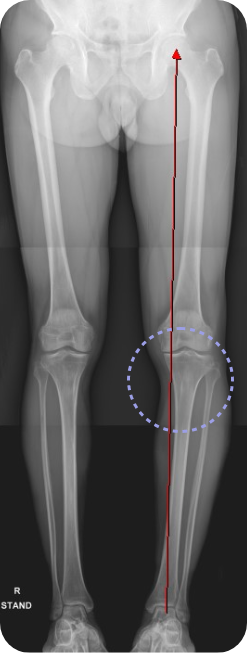

무릎 내측 관절면의 관절염이 심한 경우 관절 간격이 좁아지게 되면서 다리가 O 자형으로 변하게 됩니다. 이런 상태를 방치하게 되면 무릎 내측에 실리는 체중 부하가 늘어나면서 관절 간격이 더 좁아지게 되는 악순환이 이어지게 되는데, 이런 경우 다리의 모양을 1자형 혹은 X자형으로 만들어 무릎 관절 내측에 실리는 체중 부하를 줄이고, 관절염의 진행을 막을 수 있는 수술 방법이 근위경골 교정 절골술 입니다.